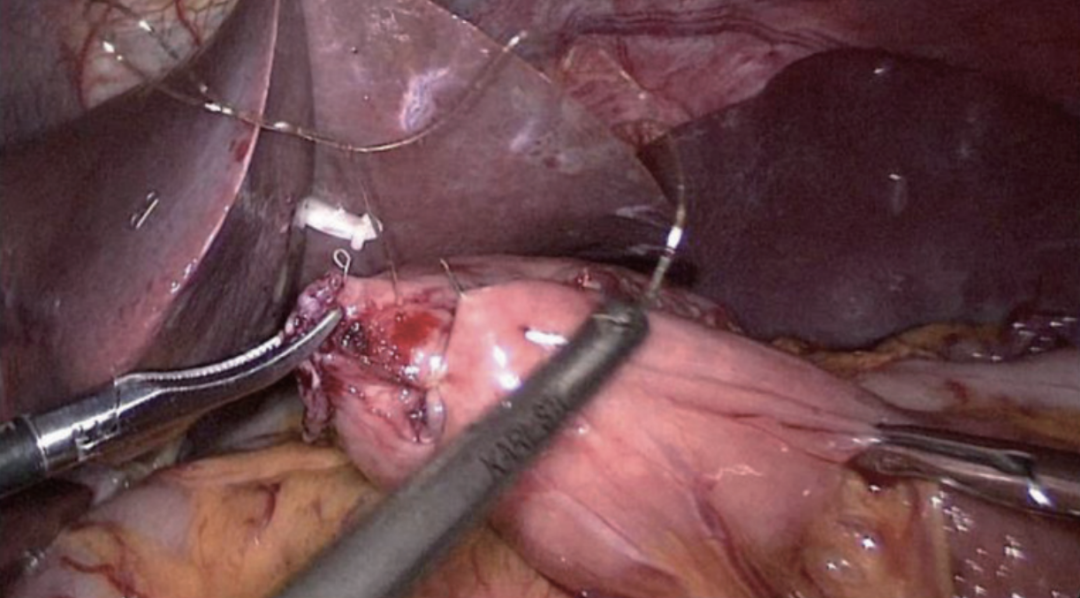

切开食管残端左侧角(图20),将直线吻合器钉仓臂插入远端空肠断端对系膜缘小口(图21),并在胃管引导下将抵钉臂插入食管残端左侧角开口(图22),行食管-空肠逆蠕动侧侧吻合,即功能性端端吻合(FETE吻合),用直线切割吻合器关闭共同开口(图23)。FETE吻合要求共同开口的关闭方向与食管空肠的切割闭合线或空肠长轴垂直,以预防出现吻合口狭窄。为了更好关闭共同开口,预缝共同开口3针作牵引(图24)。

图23 关闭食管空肠共同开口

图24 食管空肠FETE吻合口